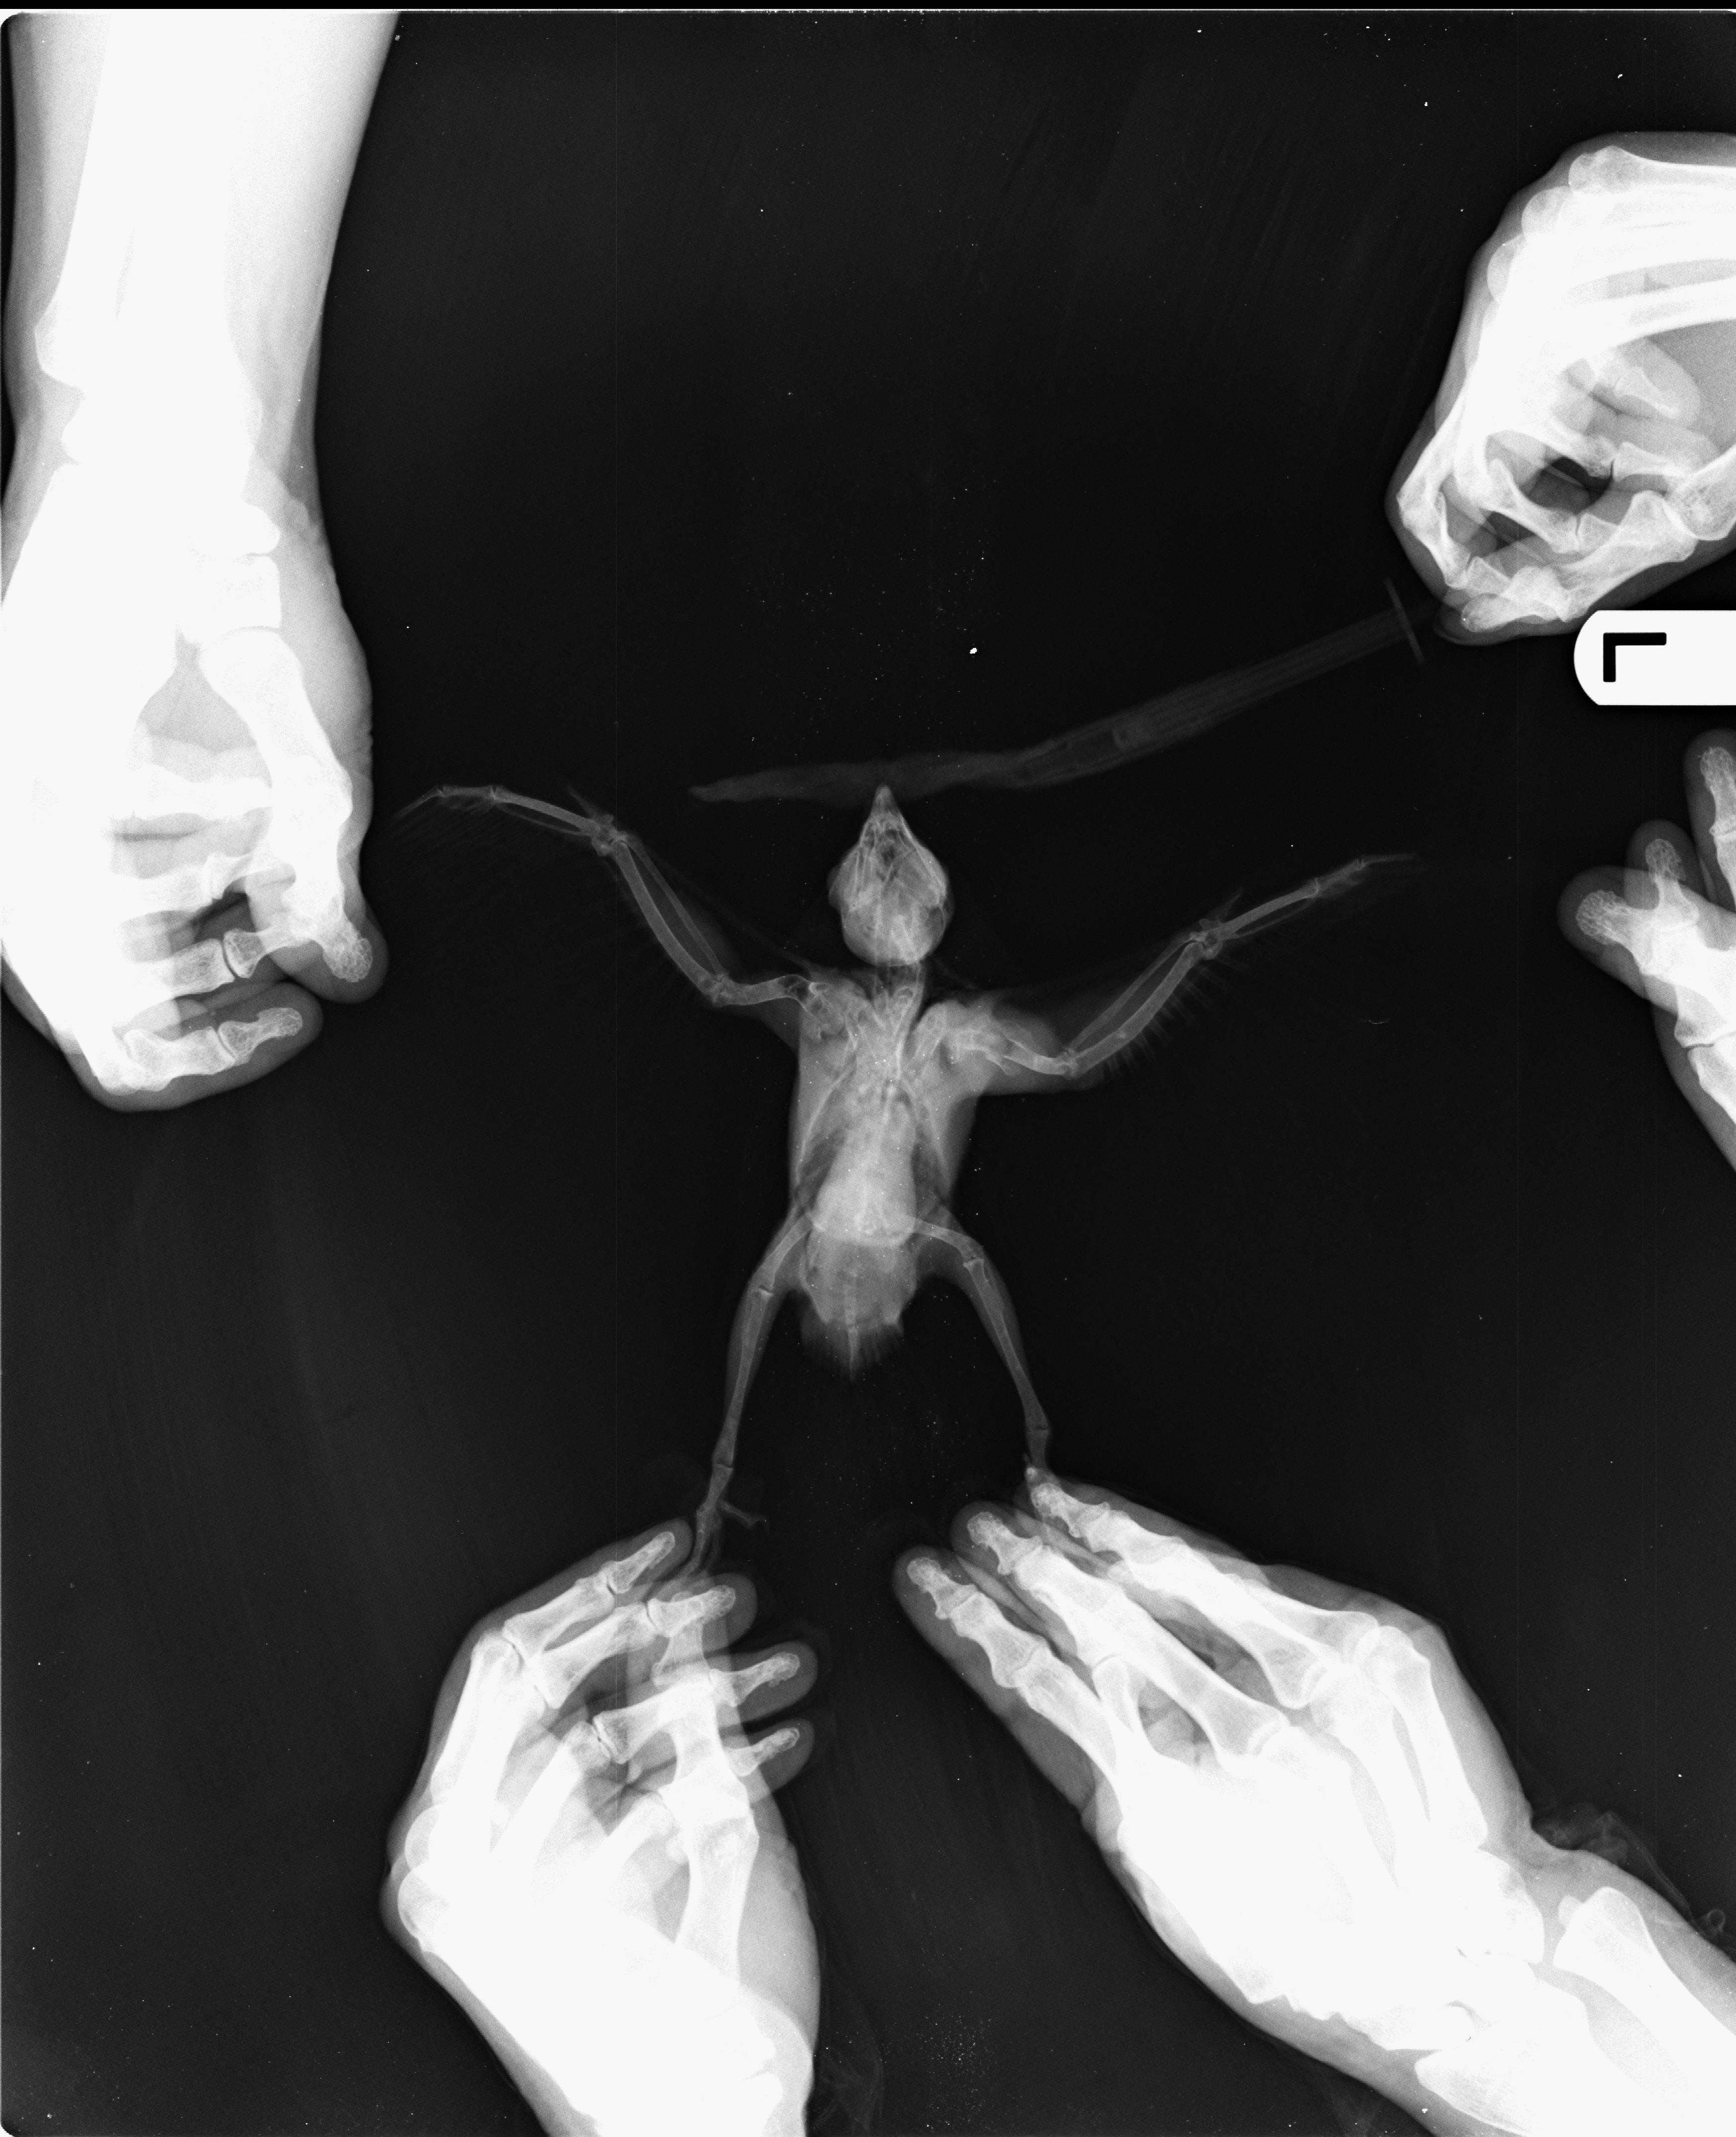

조류 엑스레이(X-Ray) 정상사진 작성자가람캡틴|작성시간22.04.25|조회수51 목록 댓글 0 글자크기 작게가 글자크기 크게가 다음검색 현재 게시글 추가 기능 열기 북마크 공유하기 신고 센터로 신고 댓글 댓글 0 댓글쓰기 답글쓰기 댓글 리스트